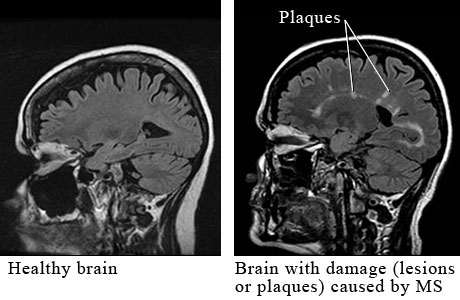

Multiple sclerosis (MS) is a chronic neurological disease of the central nervous system, specifically involving the brain, spinal cord, and optic nerves. The brain, spinal cord, and optic nerves are connected to one another by nerve fibers. A protein coating called myelin surrounds and protects the nerve fibers. Myelin can become inflamed or damaged. This is called demyelination. In MS, immune cells from blood vessels enter the brain, spinal cord, or optic nerves and cause areas of inflammation, demyelination, and nerve damage. These damaged areas are called lesions or plaques.

Magnetic resonance imaging (MRI) is a test that uses a magnetic field and pulses of radio wave energy to make pictures of organs and structures inside the body. For an MRI test, the area of the body being studied is placed inside a special machine that has a strong magnet. MRI can be used to look for problems in the brain, such as lesions or plaques caused by MS.